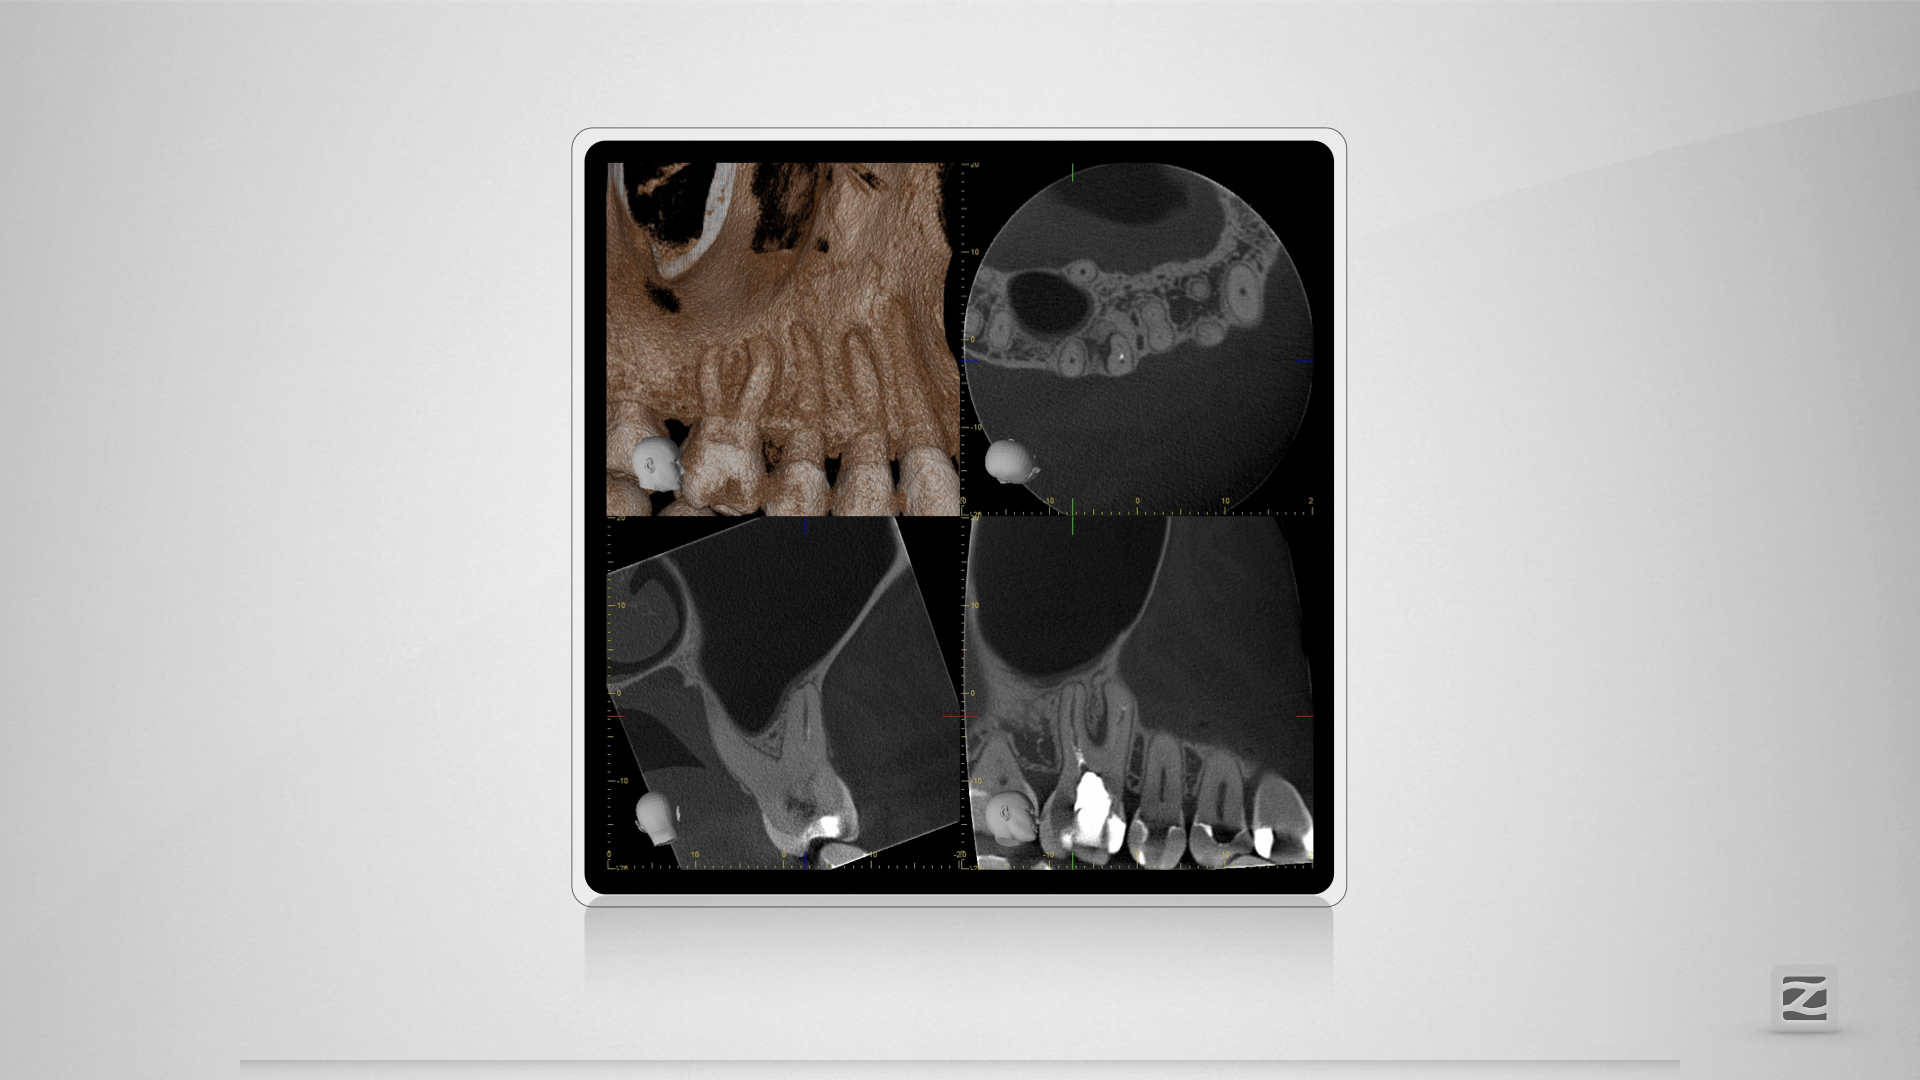

16D.003

Blue(s)